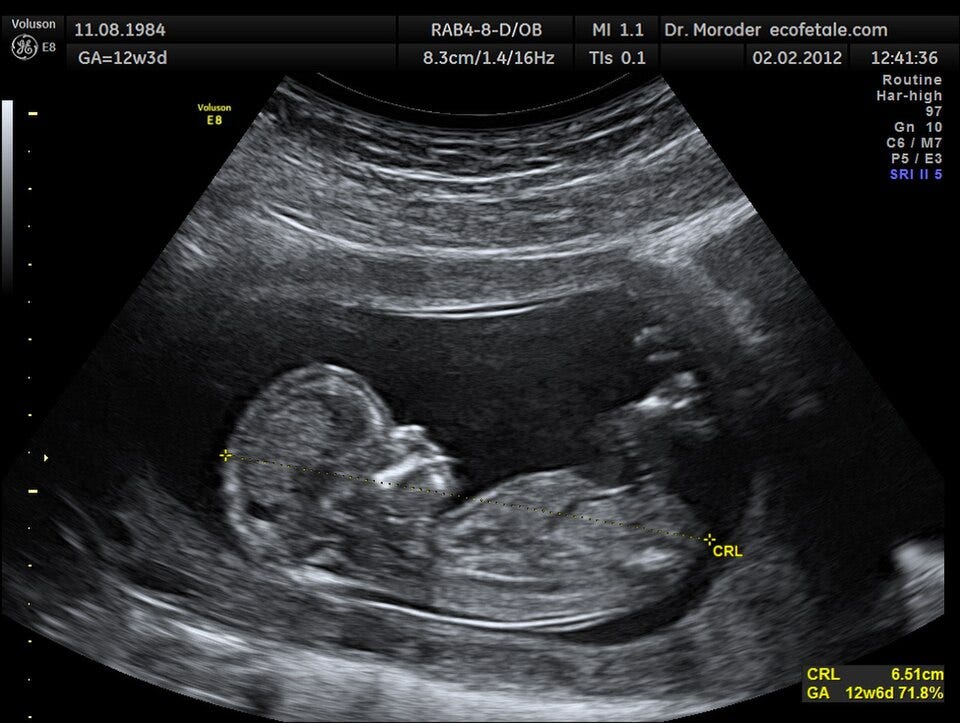

In the second half of the 20th century and the early 21st century, obstetrics began to balance medical safety with respect for natural physiology. Epidural analgesia became widespread, greatly improving pain management during labor, while ultrasound and prenatal screening made it possible to closely monitor fetal development before birth. At the same time, movements promoting more natural childbirth emerged, emphasizing midwife-led care, birthing centers, freedom of movement and position, and greater involvement of parents. Thus, after the 19th century, obstetrics evolved into a highly safe medical practice while striving to preserve a more humane and individualized experience of birth.

Au cours de la seconde moitié du XXᵉ siècle et au début du XXIᵉ siècle, l’obstétrique cherche à concilier sécurité médicale et respect de la physiologie. L’analgésie péridurale se diffuse largement, améliorant la prise en charge de la douleur, tandis que l’échographie et les examens prénataux permettent de suivre le développement du fœtus avant la naissance. Parallèlement, des mouvements en faveur d’un accouchement plus naturel émergent : maisons de naissance, accompagnement global par les sages-femmes, liberté de position et place accrue des parents. Ainsi, après le XIXᵉ siècle, l’obstétrique évolue vers une pratique hautement sécurisée, tout en cherchant à redonner une dimension humaine et personnalisée à la naissance.

Major instruments and tools have shaped obstetrics over time. One of the earliest was the obstetric forceps, developed in the early 17th century (around 1630) by the Chamberlen family, allowing assisted vaginal delivery. The stethoscope, invented in 1816 by René Laennec, was later adapted for fetal heart monitoring in the 19th century. In the 20th century, technological advances transformed pregnancy care: ultrasound imaging was introduced into obstetrics in the 1950s, revolutionizing prenatal diagnosis, while electronic fetal heart monitoring became widespread in the 1960s–1970s. Surgical tools also evolved, making the cesarean section far safer than in earlier centuries.

Les principaux instruments et outils ont profondément marqué l’histoire de l’obstétrique. L’un des plus anciens est le forceps obstétrical, mis au point au début du XVIIᵉ siècle (vers 1630) par la famille Chamberlen, permettant d’assister l’extraction du bébé. Le stéthoscope, inventé en 1816 par René Laennec, est ensuite utilisé pour écouter le cœur fœtal au XIXᵉ siècle. Au XXᵉ siècle, les progrès techniques transforment le suivi de la grossesse : l’échographie obstétricale, introduite dans les années 1950, révolutionne le diagnostic prénatal, tandis que le monitoring du rythme cardiaque fœtal se généralise dans les années 1960–1970. Les instruments chirurgicaux modernes rendent également la césarienne beaucoup plus sûre qu’auparavant.